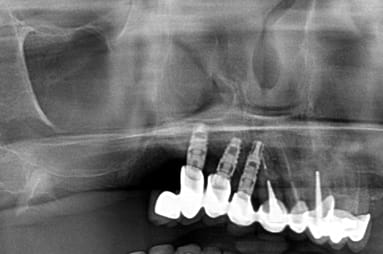

Bonjour, reconnaissez-vous la marque et le modèle de l'implant 47 ? Merci

Sans blague…..ces implants sont des Zimmer TSV

> Sans blague…..ces implants sont des Zimmer TSV

Es ce que quelqu'un aurai la reference de ses implants????

une radio mieux centrée serait idéale pour être certain à 100%.....mais ils ont quand même une bonne gueule de TBR conic....

https://www.spotimplant.com/fr/implants-dentaire/tbr/conic

Merci pour votre retour....je vous met une radio panoramique...j'ai pas mieux desolé....